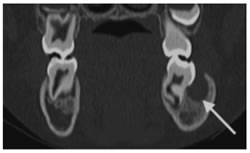

Figure 5: Dentigerous cyst. A–C, Axial (A), coronal (B), and volume-rendering 3D (C) CT views show well-circumscribed unilocular radiolucent lesion (arrows) containing crown of unerupted second molar (tooth 31)

.

Figure 6: Dentigerous cyst. (A) Coronal bone CT shows a large cystic mass extending from around the crown and cemental- enamel junction (CEJ, arrows) of an unerupted tooth. The tooth is displaced superiorly, whereas the leading edge of the cyst has displaced surrounding unerupted teeth inferiorly. (B) Axial T1- weighted magnetic resonance (MR) image of a dentigerous cyst shows a sharply marginated hyper-intense cystic mass (long arrow). Compare the hyperintensity of the cyst with the iso-intense (cf. muscle) signal of the associated mucosal thickening in the maxillary sinus (short arrow).